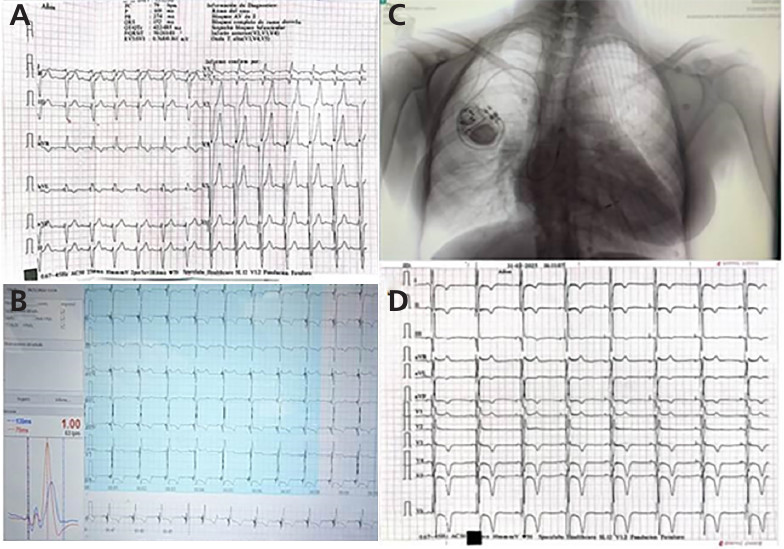

-ECG: sensado auricular y estimulación ventricular 60 lpm con ESV aisladas (Figura 1A)

Electrocardiograma post implante: Ritmo sinusal 60 lpm, QRS 135 ms con imagen rSR en V1 (Figura 1B y 1D)

Placa de tórax: catéteres normoinsertos sin complicaciones (Figura 1 C)

A ECG pre implante: ritmo de marcapasos bicameral con imagen de BCRI. B.ECG durante el implante con QRS 135 ms y patente rSR en v1. C. Placa de tórax post implante. D. ECG post implante. QRS 135 ms. Ondas T negativas cara anterolateral (memoria electrotónica).